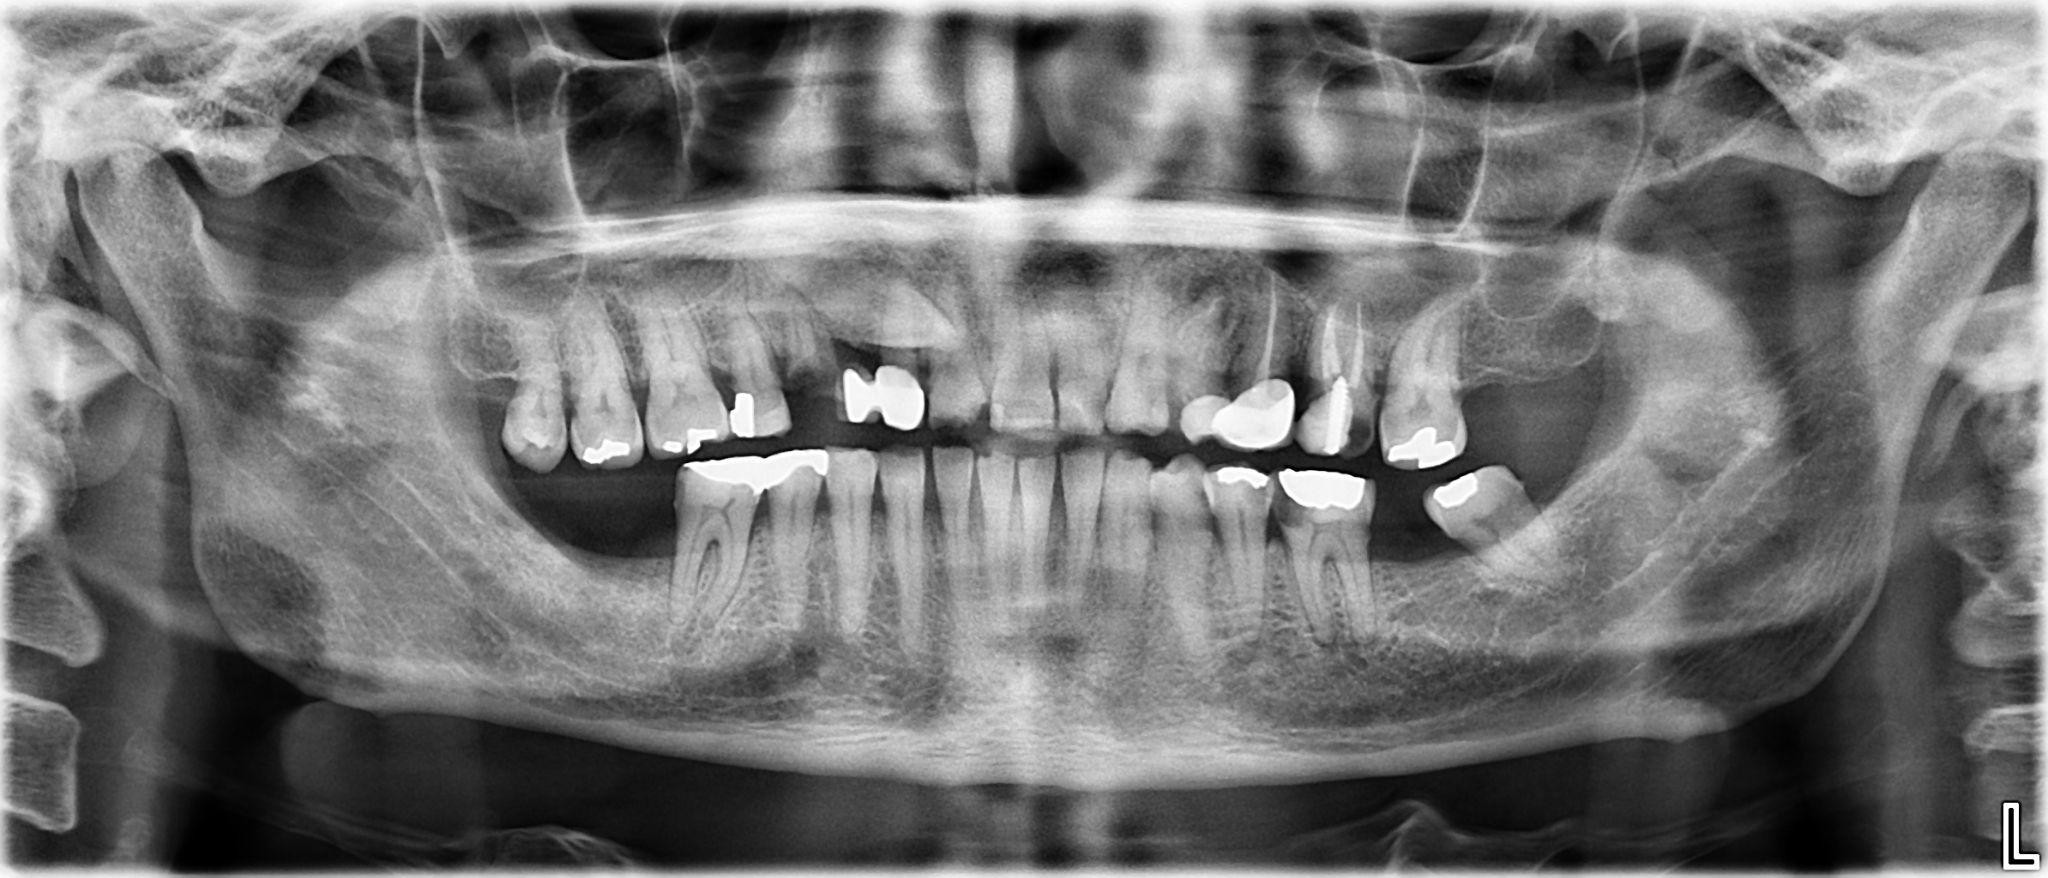

5. What options can be selected for the first quadrant of this panoramic X ray?

6. What options can be selected for the second quadrant of this panoramic X ray?

7. What options can be selected for the third quadrant of this panoramic X ray?

8. What options can be selected for the forth quadrant of this panoramic X ray?